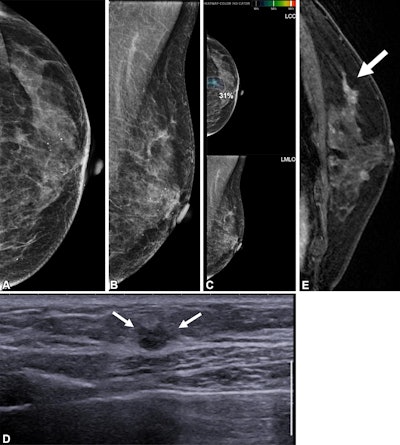

Images depict a 65-year-old patient with contralateral second breast cancer 6.3 years after right mastectomy. (A) Left craniocaudal and (B) mediolateral oblique mammograms assessed as benign. (C) The AI algorithm outlined a lesion with a score of 31 on the craniocaudal view. (D) A supplemental axial ultrasound scan, which was obtained on the same day as the mammogram, shows an irregular hypoechoic mass (arrows) in the left upper central breast. (E) Preoperative sagittal contrast-enhanced T1-weighted MRI scan shows the corresponding enhancing mass (arrow) in the left upper center. The mass was proven to be ductal carcinoma in situ.Images depict a 65-year-old patient with contralateral second breast cancer 6.3 years after right mastectomy. (A) Left craniocaudal and (B) mediolateral oblique mammograms assessed as benign. (C) The AI algorithm outlined a lesion with a score of 31 on the craniocaudal view. (D) A supplemental axial ultrasound scan, which was obtained on the same day as the mammogram, shows an irregular hypoechoic mass (arrows) in the left upper central breast. (E) Preoperative sagittal contrast-enhanced T1-weighted MRI scan shows the corresponding enhancing mass (arrow) in the left upper center. The mass was proven to be ductal carcinoma in situ.RSNA